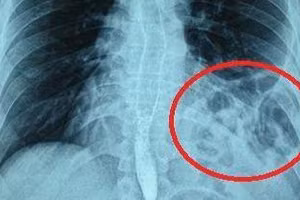

GD&TĐ - Nam thanh niên 25 tuổi bị ho, tức ngực, nghĩ mình bị hậu Covid-19 nên tự điều trị, sau một thời gian không khỏi đi khám phát hiện bị vỡ cơ hoành.